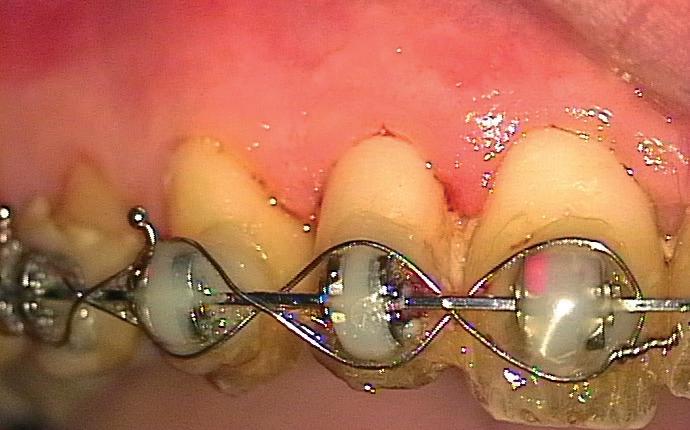

Het isoleren van het werkgebied is belangrijk. Op deze manier krijgt de behandelaar meer controle over het werkgebied en is werken onder microscopisch zicht mogelijk. Eventueel kan er gebruik gemaakt worden van de ‘split dam techniek’, zodat het subgingivale gebied toegankelijker is. Het (opnieuw) plaatsen van het cofferdamvel na preparatie is ook een mogelijkheid (afbeelding 1 en 2).

Stap 2: Preparatie van element en gingiva

Verwijder carieus tandweefsel en maak bij twijfel gebruik van een cariësdetector. In veel gevallen zal het voorkomen dat je subgingivaal eindigt. Gingiva dat in de preparatie ligt kun je verwijderen met bijvoorbeeld een elektrotoom. Ikzelf maak gebruik van

een draadloze warmtespreader, de Superendo Alpha (afbeelding 3 en 4).

Stap 3: Kies de matrix

Kies de juiste hoogte matrixband van het V3 systeem. Ideaal gezien steunt de matrixband op het tandvlees en eindigt de bovenzijde van de matrix ter hoogte van de randlijst van het element (afbeelding 5).

Stap 4: Plaats de gemodificeerde wig

Plaats een afgeknipte wig. In bijna alle gevallen gebruik ik de Wizard Wedge Wide base. Hierbij is het belangrijk dat de wig geplaatst wordt aan de zijde waar het minste tandweefsel verloren is gegaan. Zorg ervoor dat de wig direct vastloopt. Indien dit niet het geval is, dan dient de wig ingekort te worden met behulp van een schaartje en opnieuw geplaatst te worden. De wig sluit dus de bodem van de box niet af, zoals je normaal gesproken met een wig wel doet (afbeelding 6 en 7).